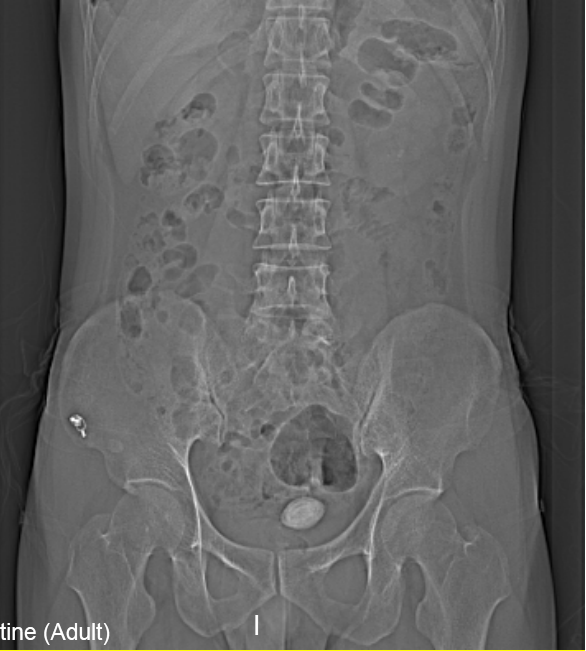

“醫(yī)生我尿不出,尿里有血,快幫幫我”。近日,在溫州市人民醫(yī)院泌尿外科門診一位男青年向坐診的黃來劍主任求助,經(jīng)驗(yàn)豐富的黃主任在了解基本病情后,特意觸摸了一下患者恥骨上區(qū),并囑咐患者進(jìn)行泌尿系平片檢查,結(jié)果在意料之中也出乎意料之外。意料之中的是患者診斷如黃主任所想膀胱結(jié)石進(jìn)入尿道卡住了,意料之外的是結(jié)石直徑達(dá)到了35mm,像蛋黃大小了,這對年輕患者來說并不常見,堵住了尿道,把患者痛的夠嗆。

▲患者影像學(xué)檢查